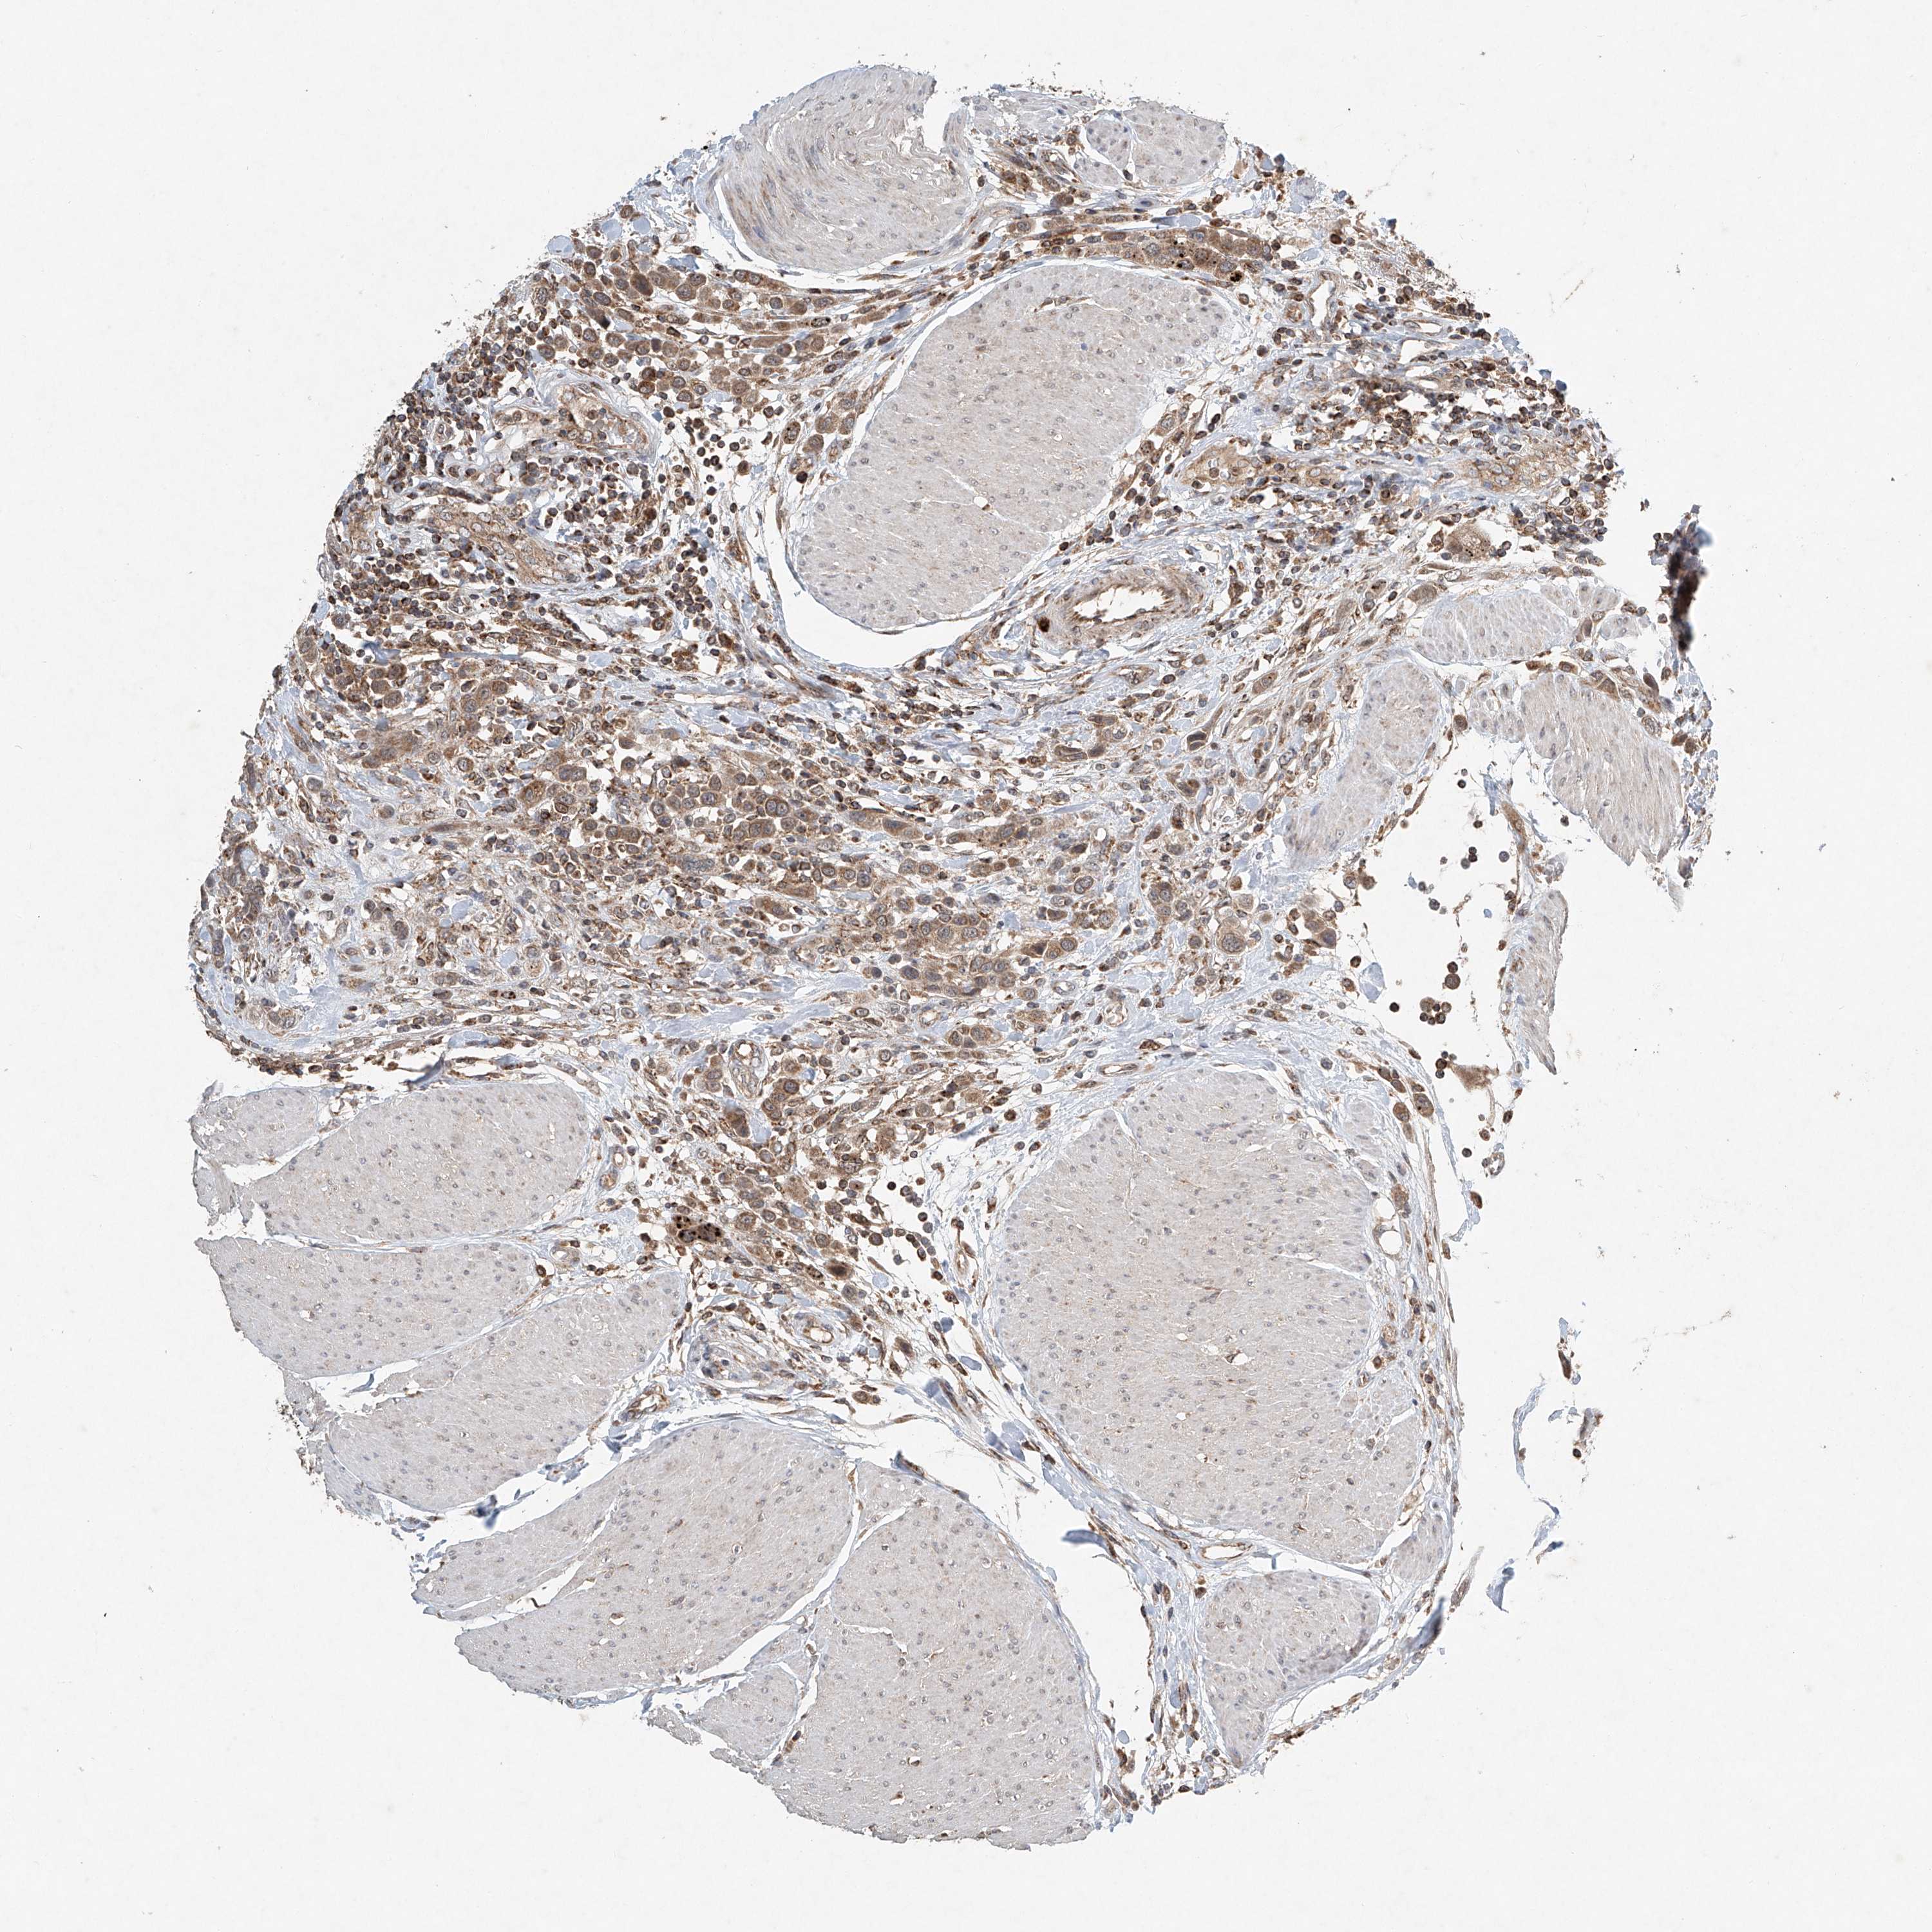

UROTHELIAL CANCER - Protein expressioni

A mouse-over function shows sample information and annotation data. Click on an image to view it in a full screen mode. Samples can be filtered based on level of antibody staining by selecting one or several of the following categories: high, medium, low and not detected. The assay and annotation is described here.

Note that samples used for immunohistochemistry by the Human Protein Atlas do not correspond to samples in the TCGA dataset.

Antibody stainingi

Antibody staining in the annotated cell types in the current human tissue is reported as not detected, low, medium, or high, based on conventional immunohistochemistry profiling in selected tissues. This score is based on the combination of the staining intensity and fraction of stained cells.

Each image is clickable and will lead to virtual microscopy that enables deeper exploration of all samples and also displays staining intensity scores, fraction scores and subcellular localization as well as patient and tissue information for each sample.

Antibody HPA031157

Staining

High

Medium

Low

Not detected

Intensity

Strong

Moderate

Weak

Negative

Quantity

>75%

75%-25%

<25%

None

Location

Nuclear

Cytoplasmic/membranous

Cytoplasmic/membranous,nuclear

Urothelial carcinoma, Low grade

Urothelial carcinoma, High grade